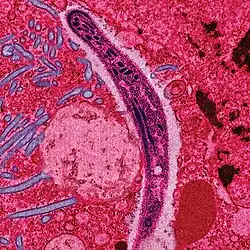

| False-colored electron micrograph of a sporozoite | |